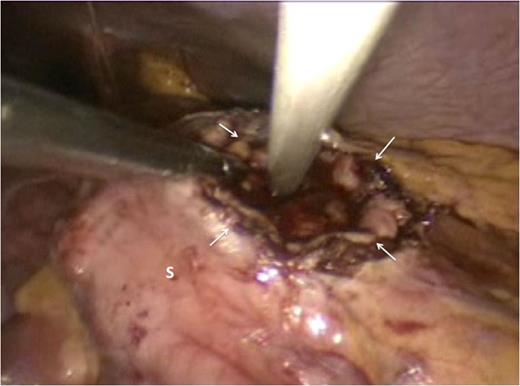

Attention was then turned to the pseudocyt. The stomach was seen draped over the pseudocyst, with small bowel adherent to its greater curvature. Therefore, we decided to use an anterior approach. A gastrostomy was created to open the body of the stomach (Fig. 3). This allowed the scope to enter the gastric lumen. The area of maximal pointing of the pseudocyst into the posterior wall was identified. A second gastrostomy was created at the posterior stomach wall (Fig. 4) and this was developed to enter and then decompress the pseudocyst lumen. A 60 mm Endo-GIA stapler was introduced into the tract (Fig. 5) and used to create a sturdy anastomosis between the lumina of pseudocyst and stomach (Fig. 6). The hanging manoeuvre was then used to suspend the anterior stomach wall in order to facilitate closure with the endo-GIA stapler (Fig. 7). The single ‘S’ incision in the abdomen was closed in layers. No cultures were taken since there was no clinical or biochemical evidence of infection.

Cystogastrostomy was performed using the anterior approach. An incision was made in the anterior wall of the body of the stomach to allow entry into the gastric lumen.

The gastric lumen was entered through the incision at the anterior stomach wall (margins indicated by white arrows). Conventional straight laparoscopic instrument can be seen developing an tunnel at the posterior stomach wall at the area where bulging from the pseudocyst is most prominent.